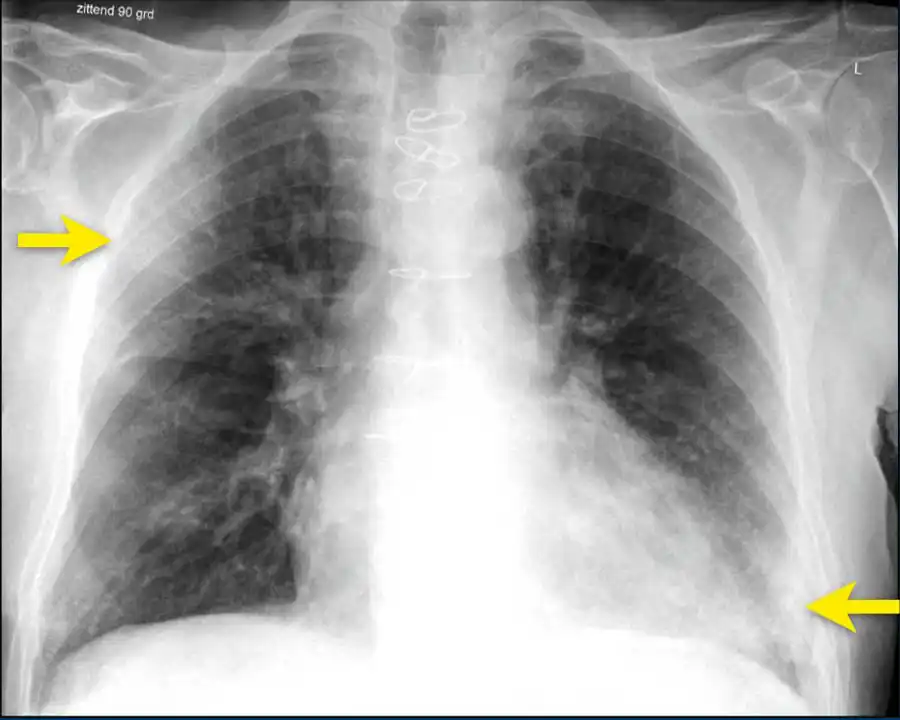

Doctors often see the aftermath on CT scans as “ground-glass opacities”—hazy areas that signal inflammation and damage.